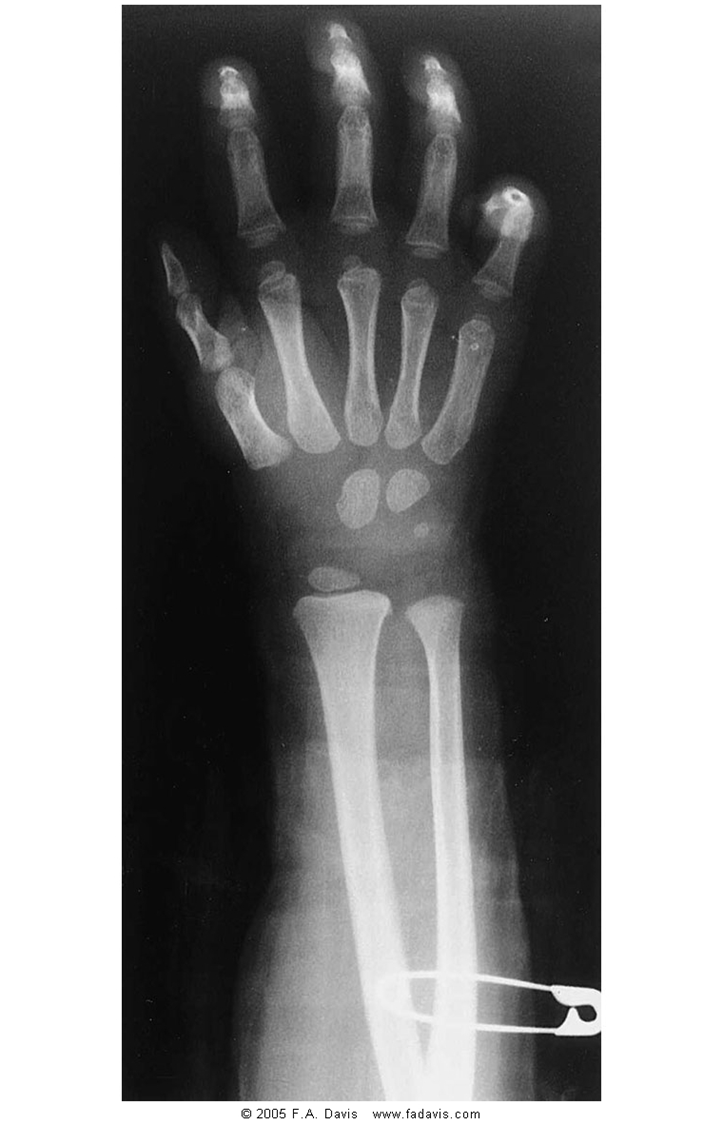

What view is this

PA wrist

Colles’ fx